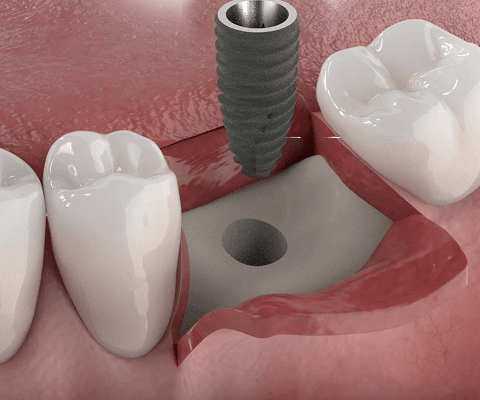

02

잇몸뼈에 임플란트를 식립

이식한 뼈에 충분한 고정력이 확보될 경우, 뼈이식과 동시에 임플란트를 심어 수술을 한 번에 마무리할 수 있습니다. 수술 횟수 감소와 빠른 회복이 큰 장점입니다.

03

이식한 뼈 위에 차폐막을 덮어 고정

차폐막은 이식한 뼈 위를 덮어 외부 자극이나 잇몸세포 침입을 막고, 뼈가 제대로 자랄 수 있도록 안정된 환경을 만들어줍니다.